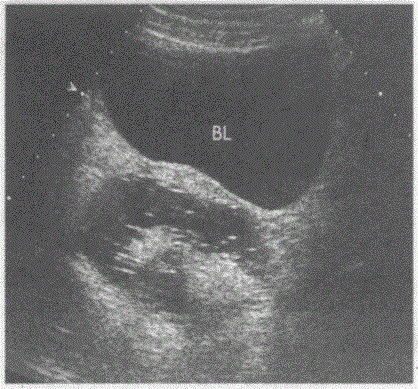

问题 临床资料:女,24岁,常规体检。 超声综合描述:右附件区可见无回声区,边界清晰,内透声不清亮,内见团状中强回声,后伴弱声影。 超声提示:

选项 A.右输卵管积液 B.右卵巢囊肿 C.右卵巢巧克力囊肿 D.右卵巢囊性畸胎瘤(发团征)

答案 D